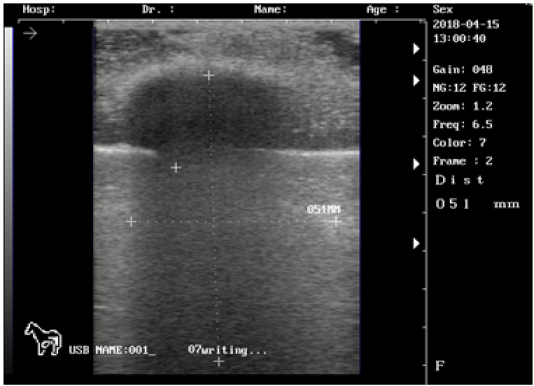

Ultrasound images of the testis of 5 months lamb showing: moderate echogenicity of the testicular parenchyma; mediastinum testicular diffusely echogenic